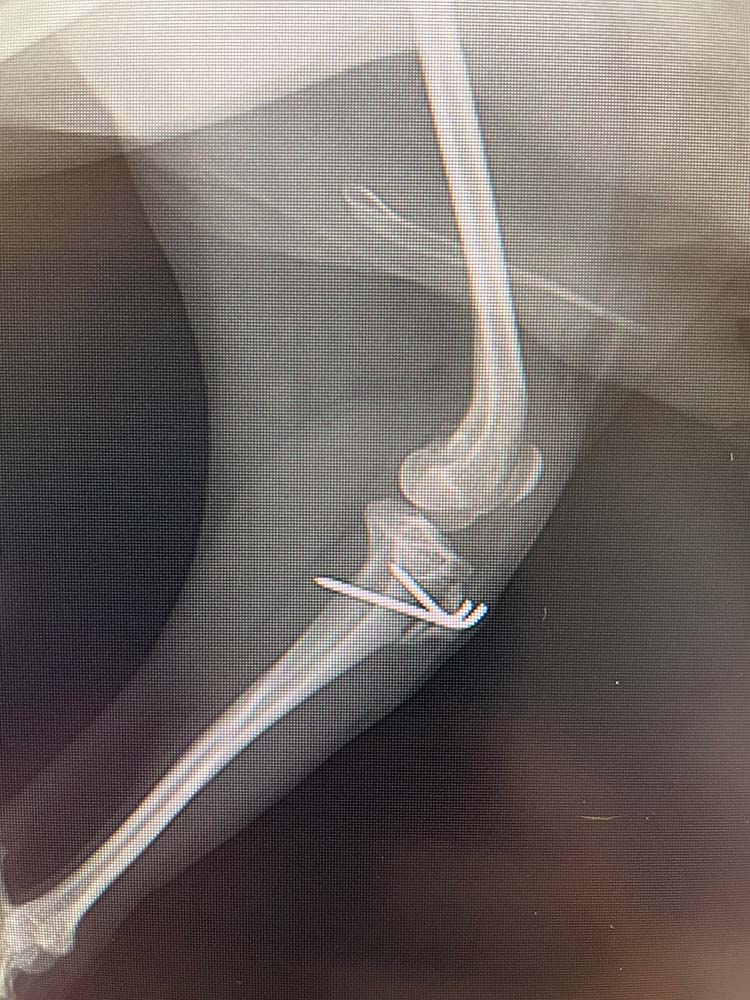

- 脛骨粗面転移

膝蓋靱帯の脛骨への付着部を骨切りし、滑車溝の真下に移動させる手技

また、脛骨粗面転移に関しては、Polaris Vetでは全ての症例での実施とはせず、脛骨の捻れの程度や膝関節における軟部組織での回旋の程度によって適応可否の判断をしています。

脛骨粗面転移は脛骨の膝蓋靱帯付着部で骨切りを行い、ずらした場所にピンで固定するという方法になります。

そのため、骨癒合が得られるまでの安静期間が長くなることや合併症発生リスクが高くなるデメリットも存在します。